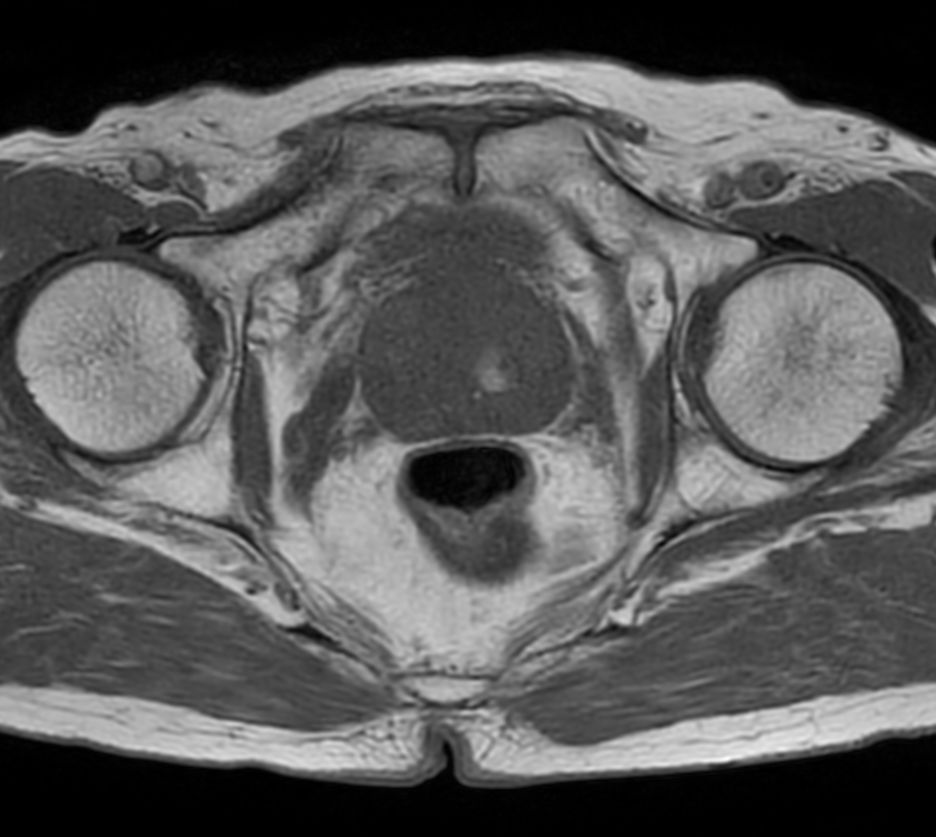

T1w TSE - Compressed SENSE